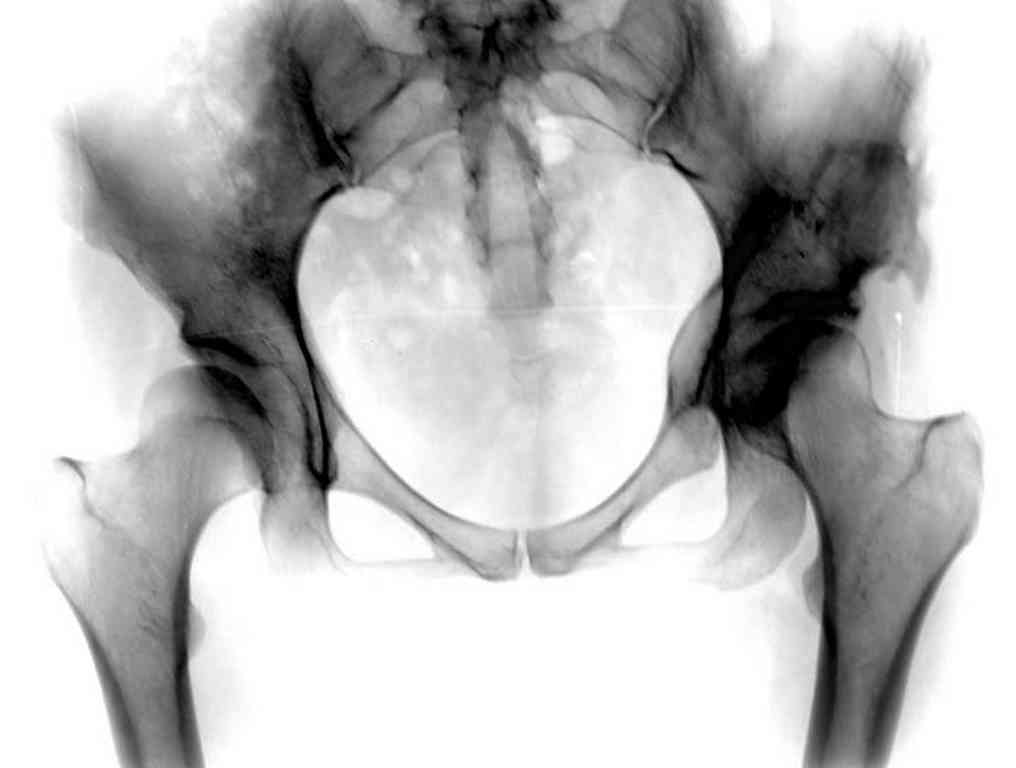

Представляю Р-снимки: обзорная, с отведением и с приведением.

Глубокоуважаемый Абдурашид. Здесь нет снимка с отведением. Если Вы сами сходили в рентгенкабинет и лично отвели пораженную конечность максимально возможно, а также дали максимально возможную внутреннюю ротацию-это одно!!!! Значит у пациентки тяжелейшая приводящая контрактура тазобедренного сустава!! И необходимо разобраться-миогенная или артрогенная? Если же Вы просто назначили указанный снимок и доверили произвести укладку рентгентехнику-это другое!!! Одному богу известно, что она делала, ведь на р-снимке отведения нет!

Все предыдущие корреспонденты предлагают вам достаточно простую вещь-смоделировать предлагаемую Вами операцию (т.е. дать отведение и внутреннюю ротацию) и посмотреть, как изменятся соотношения в суставе. Не обижайтесь, но судя по представлению клинического случая угловые величины, характеризующие пространственные соотношения в тазобедренном суставе, ваши рентгенологи не считают.

Уважаемый Игорь Владимирович. диссертации М М Камоска, и В Е Баскова я нашел, но почему-то не могу открывать, и еще в данном случае имеется дисплазия т/б за счет недоразвития крыши в/впадины да и всей подвздошной кости, маргинального вывиха или латеропозиции головки вследствие лечебных ощибок нет, головка стоит на месте. Р-граммы сделал сам, но почему-то у больной отведение и внутренная ротация стали очень болезненной, и сухожилия приводящих мышц сильно натягивается.(контрактура артро-миогенная).

Глубокоуважаемый Игорь Владимирович! Признаюсь допустил ошибку, из-за напряженности работы и нехватки времени, когда повторно внимательно посмотрел все понял и не успел исправить ошибку до Вашего поста, конечно скошенность крыши в пределах 40гр,часть головки кнаружи линии Омбредана-Перкинса , облитерация дна вертлужной впадины и т.д.-это ДМВБ.